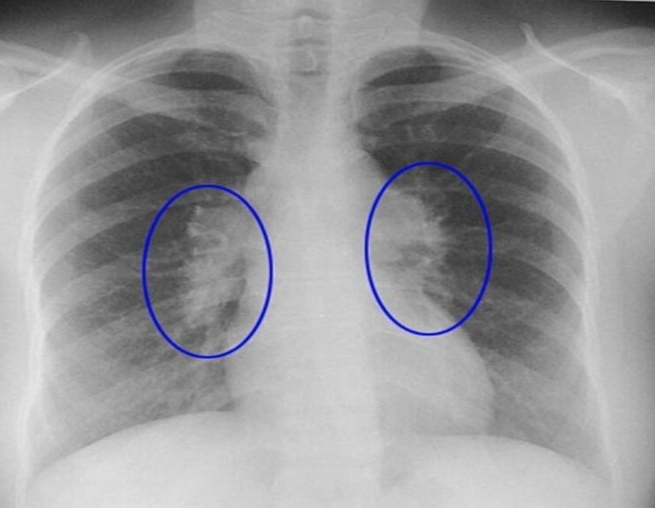

Paciente presenta adenopatía hiliar bilateral

Dx probable:

A

1. TB

2. Patogeno neumonia atipica

3. Hongos

4. Sarcoidosis